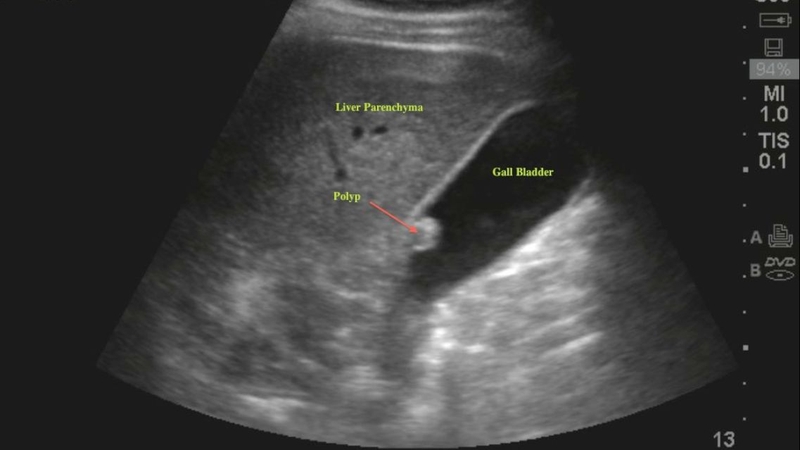

Polyp túi mật thường được phát hiện tình cờ khi siêu âm ổ bụng. Phần lớn các trường hợp polyp túi mật là lành tính, không gây triệu chứng rõ rệt. Tuy nhiên, nếu polyp phát triển với kích thước lớn hoặc có đặc điểm nghi ngờ, nguy cơ tiến triển thành ung thư túi mật sẽ tăng lên.

Đây là câu hỏi rất phổ biến với người bệnh sau khi siêu âm phát hiện polyp túi mật. Theo hướng dẫn lâm sàng và thực hành hiện nay, việc quyết định phẫu thuật không chỉ dựa vào kích thước, mà còn phải đánh giá toàn diện qua nhiều yếu tố như hình dạng, tốc độ phát triển, triệu chứng và nguy cơ ác tính.

Cụ thể, với polyp nhỏ hơn 5mm, đa phần là polyp cholesterol lành tính, thường không gây triệu chứng và không cần phẫu thuật. Người bệnh chỉ cần theo dõi bằng siêu âm định kỳ mỗi 6 - 12 tháng, nhất là nếu không có yếu tố nguy cơ kèm theo.

Trường hợp polyp có kích thước từ 5 - 9mm, người bệnh cần được theo dõi sát hơn.

Dù đây chưa phải là ngưỡng tuyệt đối để chỉ định cắt, nhưng nếu kèm theo các yếu tố như: Tuổi trên 50, polyp đơn độc (chỉ có một cái), có cuống rộng, có sỏi túi mật, hoặc polyp tăng kích thước theo thời gian,… thì bác sĩ có thể cân nhắc mổ sớm để phòng ngừa nguy cơ tiến triển ác tính.

Khi polyp đạt kích thước từ 10mm trở lên, nguy cơ ung thư túi mật tăng lên rõ rệt. Lúc này, phẫu thuật cắt túi mật được chỉ định, ngay cả khi người bệnh chưa có triệu chứng.